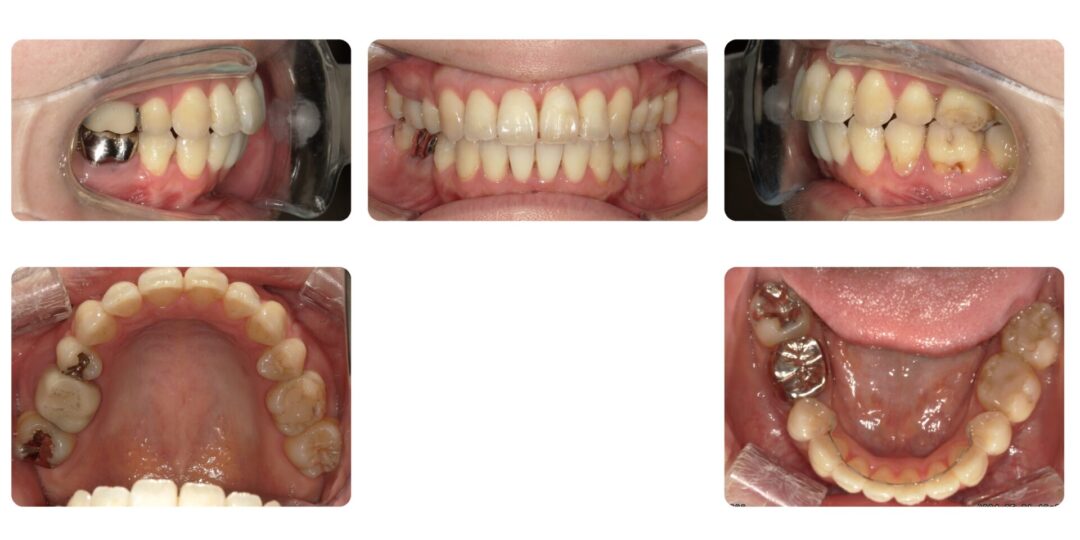

上下顎前歯唇側傾斜を伴う骨格性上顎前突|初診時28歳

成人矯正 上下顎左右4番抜歯 マルチブラケット装置による歯列矯正

2年9ヶ月